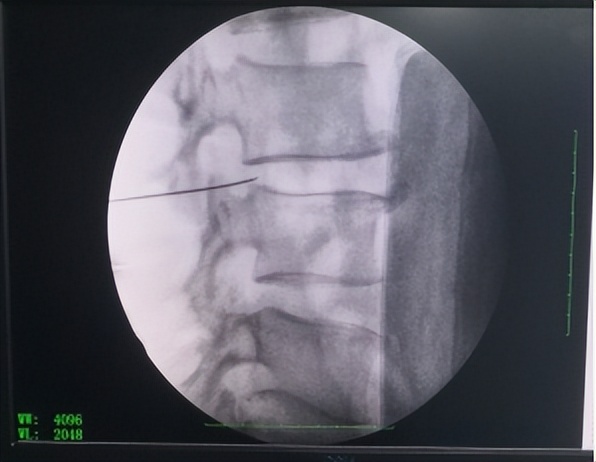

近日,庆城县岐伯中医医院疼痛科在北京海军总医院疼痛诊疗中心张建军主任的指导下成功开展了首例经皮穿刺椎间盘微创射频消融术,填补了我县该项技术的空白。

患者,白某,因间断性腰痛伴左下肢放射性疼痛、左足麻木4年余,先后就诊于西安多家医院,诊断为腰椎间盘突出症,保守治疗未取得满意治疗效果,病情时轻时重,反复发作,影响睡眠及工作,曾有医院建议行开放手术治疗,未接受。近1月上述症状复发且加重,无法正常下地行走,影响日常生活,6月3日患者来我院疼痛科求治,经科室讨论、北京海军总医院疼痛诊疗中心张建军主任会诊决定为患者实施经皮穿刺椎间盘微创射频消融术及臭氧介入治疗术。整个手术过程非常顺利,仅用时15分钟。术后患者即感左下肢放射性疼痛及左足麻木症状消失,当即可下床负重活动,术后第二天查房,患者自诉腰部无疼痛,夜间可正常睡眠,手术后5天康复出院。

经皮穿刺椎间盘微创射频消融术,是由北上广深发达城市疼痛科率先开展的一项治疗技术。主要是在椎间盘突出症患者治疗方法上的创新。椎间盘突出症患者疼痛原始治疗方法有两种,一种是物理康复治疗,比如针灸、中频、蒸汽药浴,另一种是外科开放手术。经皮穿刺椎间盘微创射频消融术是介于两种技术之间,通过影像引导将一根针穿刺至椎间盘的突出部分,通过射频的热凝消融部分椎间盘,减轻突出症状,治疗该疾病。该治疗方法具有效果确切,创伤小,术后当天即可下床活动等优点。